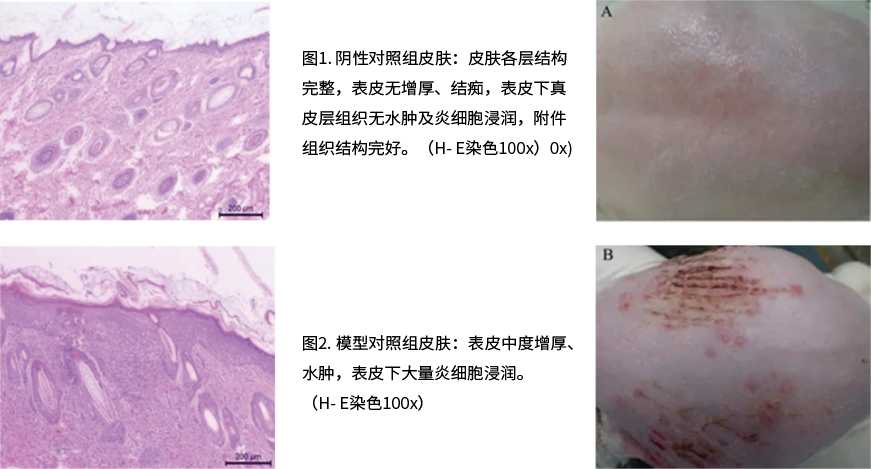

◆ 皮膚類動物疾病模型